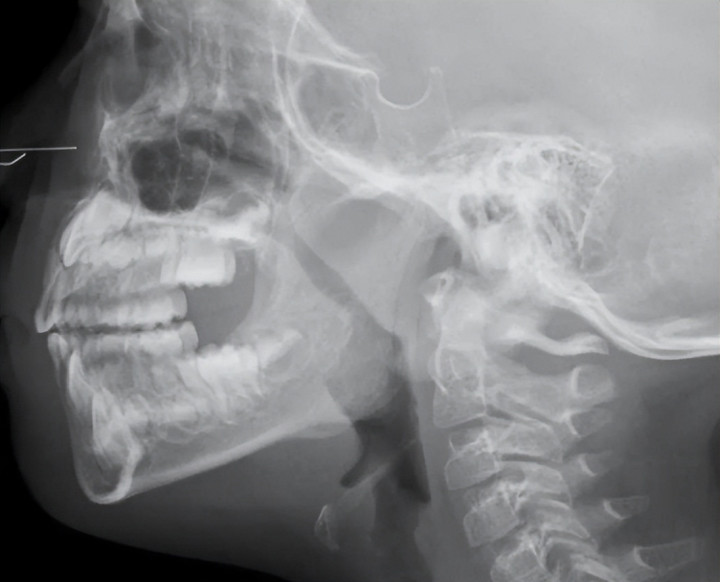

扁桃体紧紧守在咽喉要说念,像 24 小时不眠不竭的守门卫士。

尤其是6 岁畴前,扁桃体等于孩子的免疫中枢:

惟一这 4 种情况,才洽商切除(别盲目手术)

一年发炎 **≥7 次 **,判辨 2 年皆如斯

肿大到睡觉憋气、缺氧、呼吸暂停

激励肾炎、心肌炎、风湿等严重并发症

反复脓肿,药物完全无效